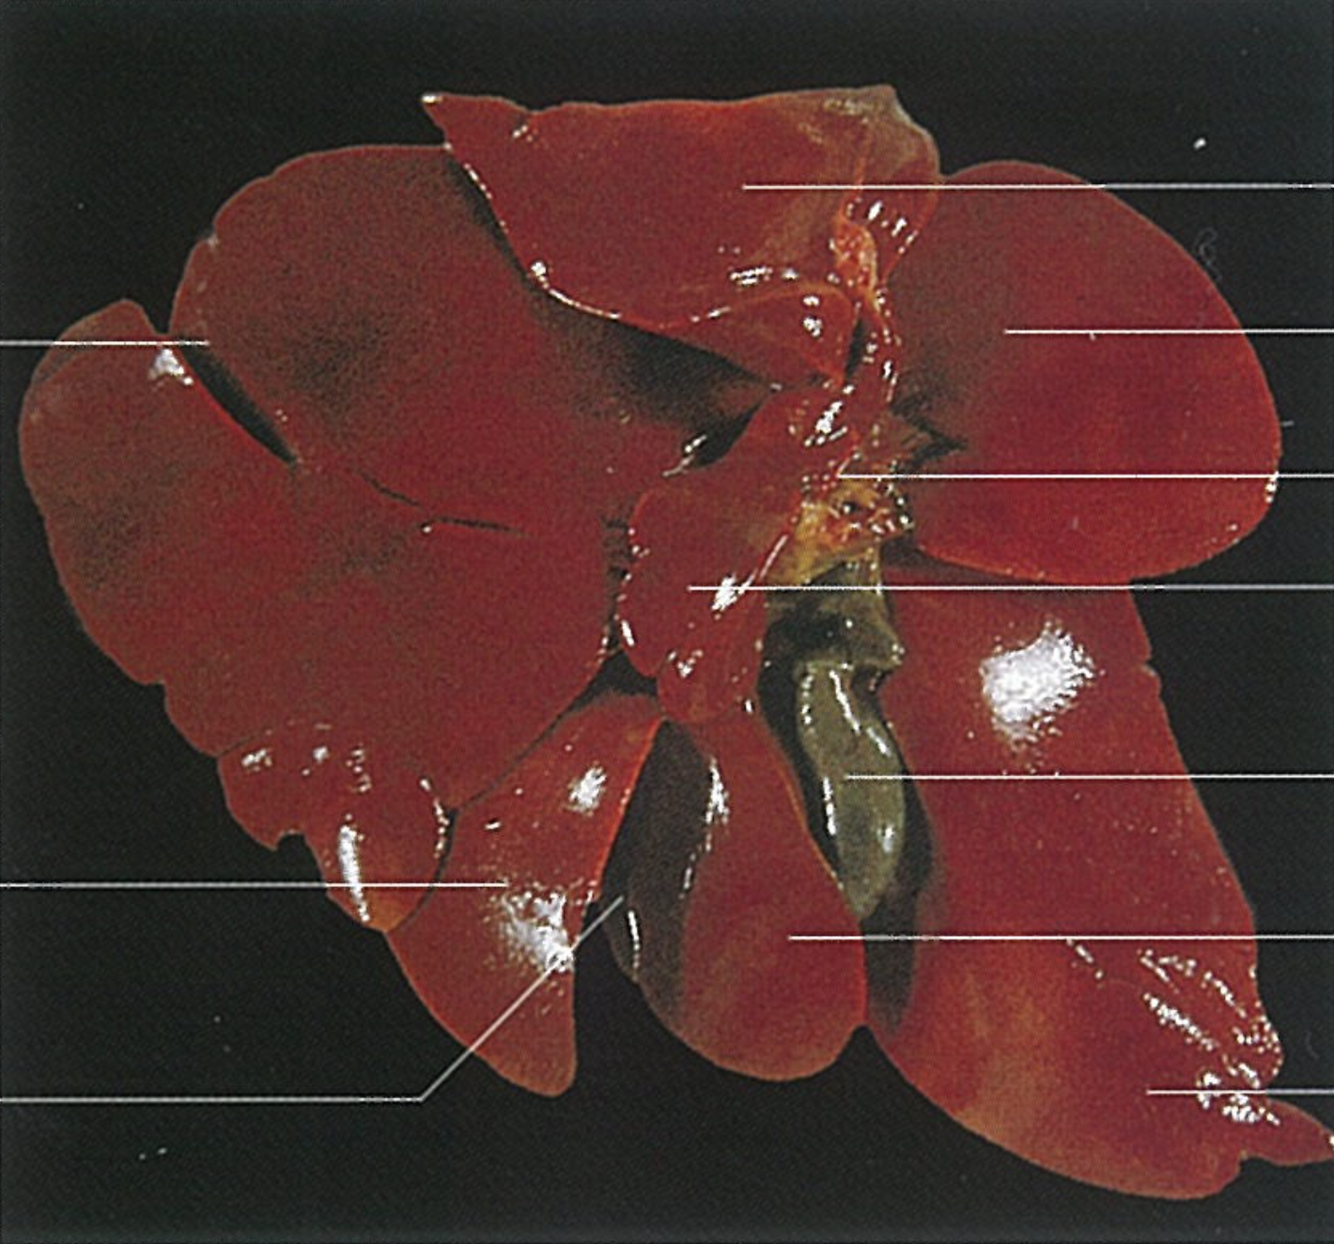

What is shown? Give the Aspect.

Liver of a Cat

What is shown? Give the Aspect

Liver of a Cat

Fascies visceralis